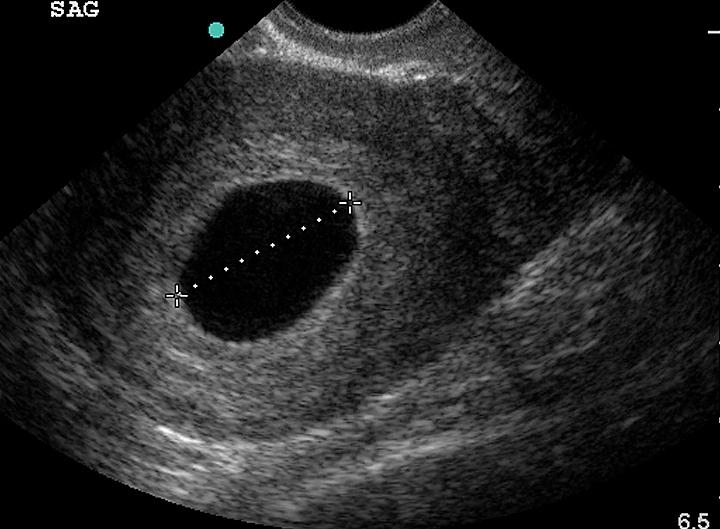

Boş gebeliğin aslında normal bir hamilelikten hiçbir farkı yoktur. Fakat ultrason kontrolünde bunun doğru olmadığı fark edilebilir. Ultrasonda gebelik kesesi içerisinde embriyo görülmesi gerekirken, embriyo görülmez. Bu durumda teşhis konur.